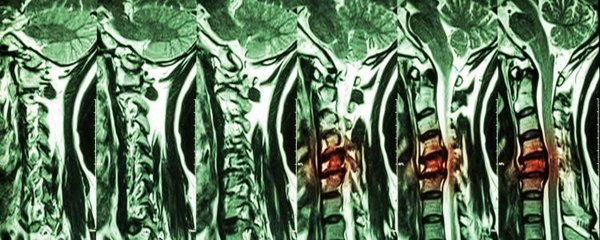

Was ist die Spondylolyse?

Bei der Spondylolyse kommt es zu einer so genannten Kontinuitätsunterbrechung der Zwischenwirbelgelenke. Die Fortsätze, die diese Gelenke bilden, gehen vom Wirbelbogen aus. Jeder Wirbelbogen hat einen Fortsatz zu dem darüber liegenden und einen zu dem darunter liegenden Wirbelkörper. Es kann zu einer Spaltbildung im Wirbelbogen kommen, wobei die Verbindung der beiden Fortsätze voneinander getrennt wird. Sind beide Zwischenwirbelgelenke betroffen (beidseitige Unterbrechung der Interartikularportion) kann das Wirbelgleiten (Spondylolisthesis) kann eine Folge sein. Hierbei rutscht der obere Wirbel im Verhältnis zum unteren nach vorne. Der Wirbel kann verschieden stark nach vorne weggleiten. Zur Diagnostik findet eine Einteilung in Schweregrade nach Meyerding statt. Es handelt sich bei der Spondylolyse um eine Fraktur, die in der Regel nicht ausheilt. Die Erkrankung kann somit nur symptomatisch oder in schweren Fällen operativ behandelt werden.

Die Spondylolyse tritt in 80 % der Fälle im Lendenwirbelsäulenbereich beim 5. Lendenwirbelkörper auf. Der 4. Lendenwirbelkörper ist der am zweithäufigsten betroffene Wirbelkörper. In anderen Wirbelsäulenabschnitten wie der BWS oder HWS kommt eine Spondylolyse nur äußerst selten vor. Sie ist häufig durch angeborene Wirbelsäulendeformitäten begünstigt und tritt dann schon im Kindes- oder Jugendalter auf. Betroffen sind häufig Kinder mit einem starken Hohlkreuz. Bestimmte Sportarten wie Turnen oder Schmetterlingschwimmen, bei denen ein vermehrtes Hohlkreuz gefordert ist, können die Entstehung der Spondylolyse begünstigen. Starke Symptome treten häufig erst im Erwachsenenalter auf. Bei einer erworbenen Spondylolyse kann eine Fraktur durch chronische, langfristige Belastung (Ermüdungsbruch) ursächlich sein, selten können auch metastasierende Tumore zu einer Spondylolyse führen. Es kann bei der Spondylolyse zu Rückenschmerzen und Verspannungen kommen. Auch eine Fehlhaltung zu Gunsten eines Hohlkreuzes ist häufig. Schmerzen treten besonders nach Belastungen auf, bei denen der Rücken in Extension (Streckung) belastet wird. Durch die fehlende Stabilität des Wirbelkörpers muss die Muskulatur vermehrt gegen die Haltung arbeiten und verspannt schnell.